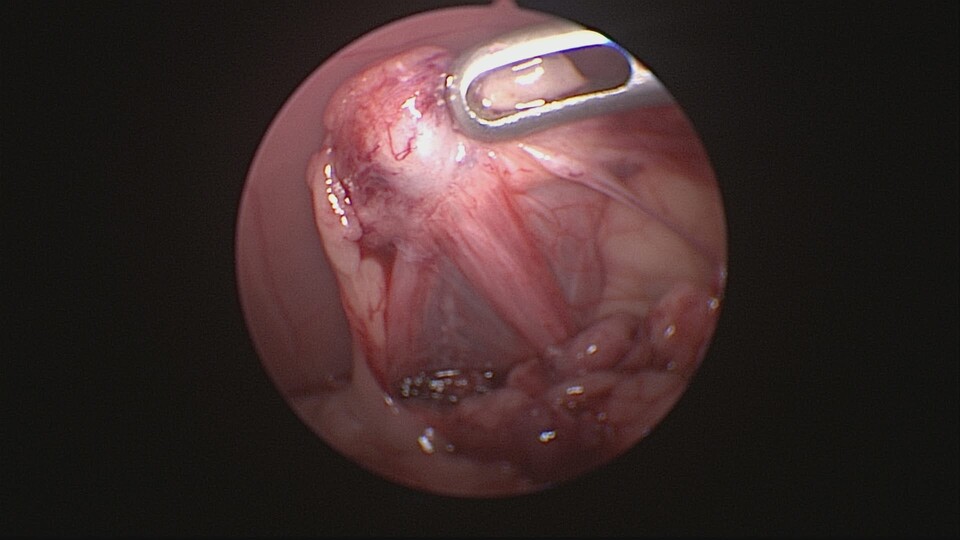

1. 傷口要小喔 (手術視野範圍越小,越不容易看清楚臟器的全貌,部分卵巢殘留或術中出血狀況也不易被察覺。追求傷口小可考慮內視鏡手術)

卵巢殘留症候群是指在進行卵巢子宮切除術(OHE)後,卻因卵巢組織未完全切除,導致體內仍有部分卵巢組織殘留,進而分泌性激素,引發類似發情的症狀。常見於狗與貓,可能會出現陰道分泌物、行為改變、乳腺腫脹等現象。

*手術視野不佳或操作困難

*腹腔沾黏使卵巢不易辨認